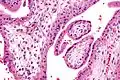

Micrografía que muestra vellosidades coriónicas. Aumento intermedio. Tinción H&E. -